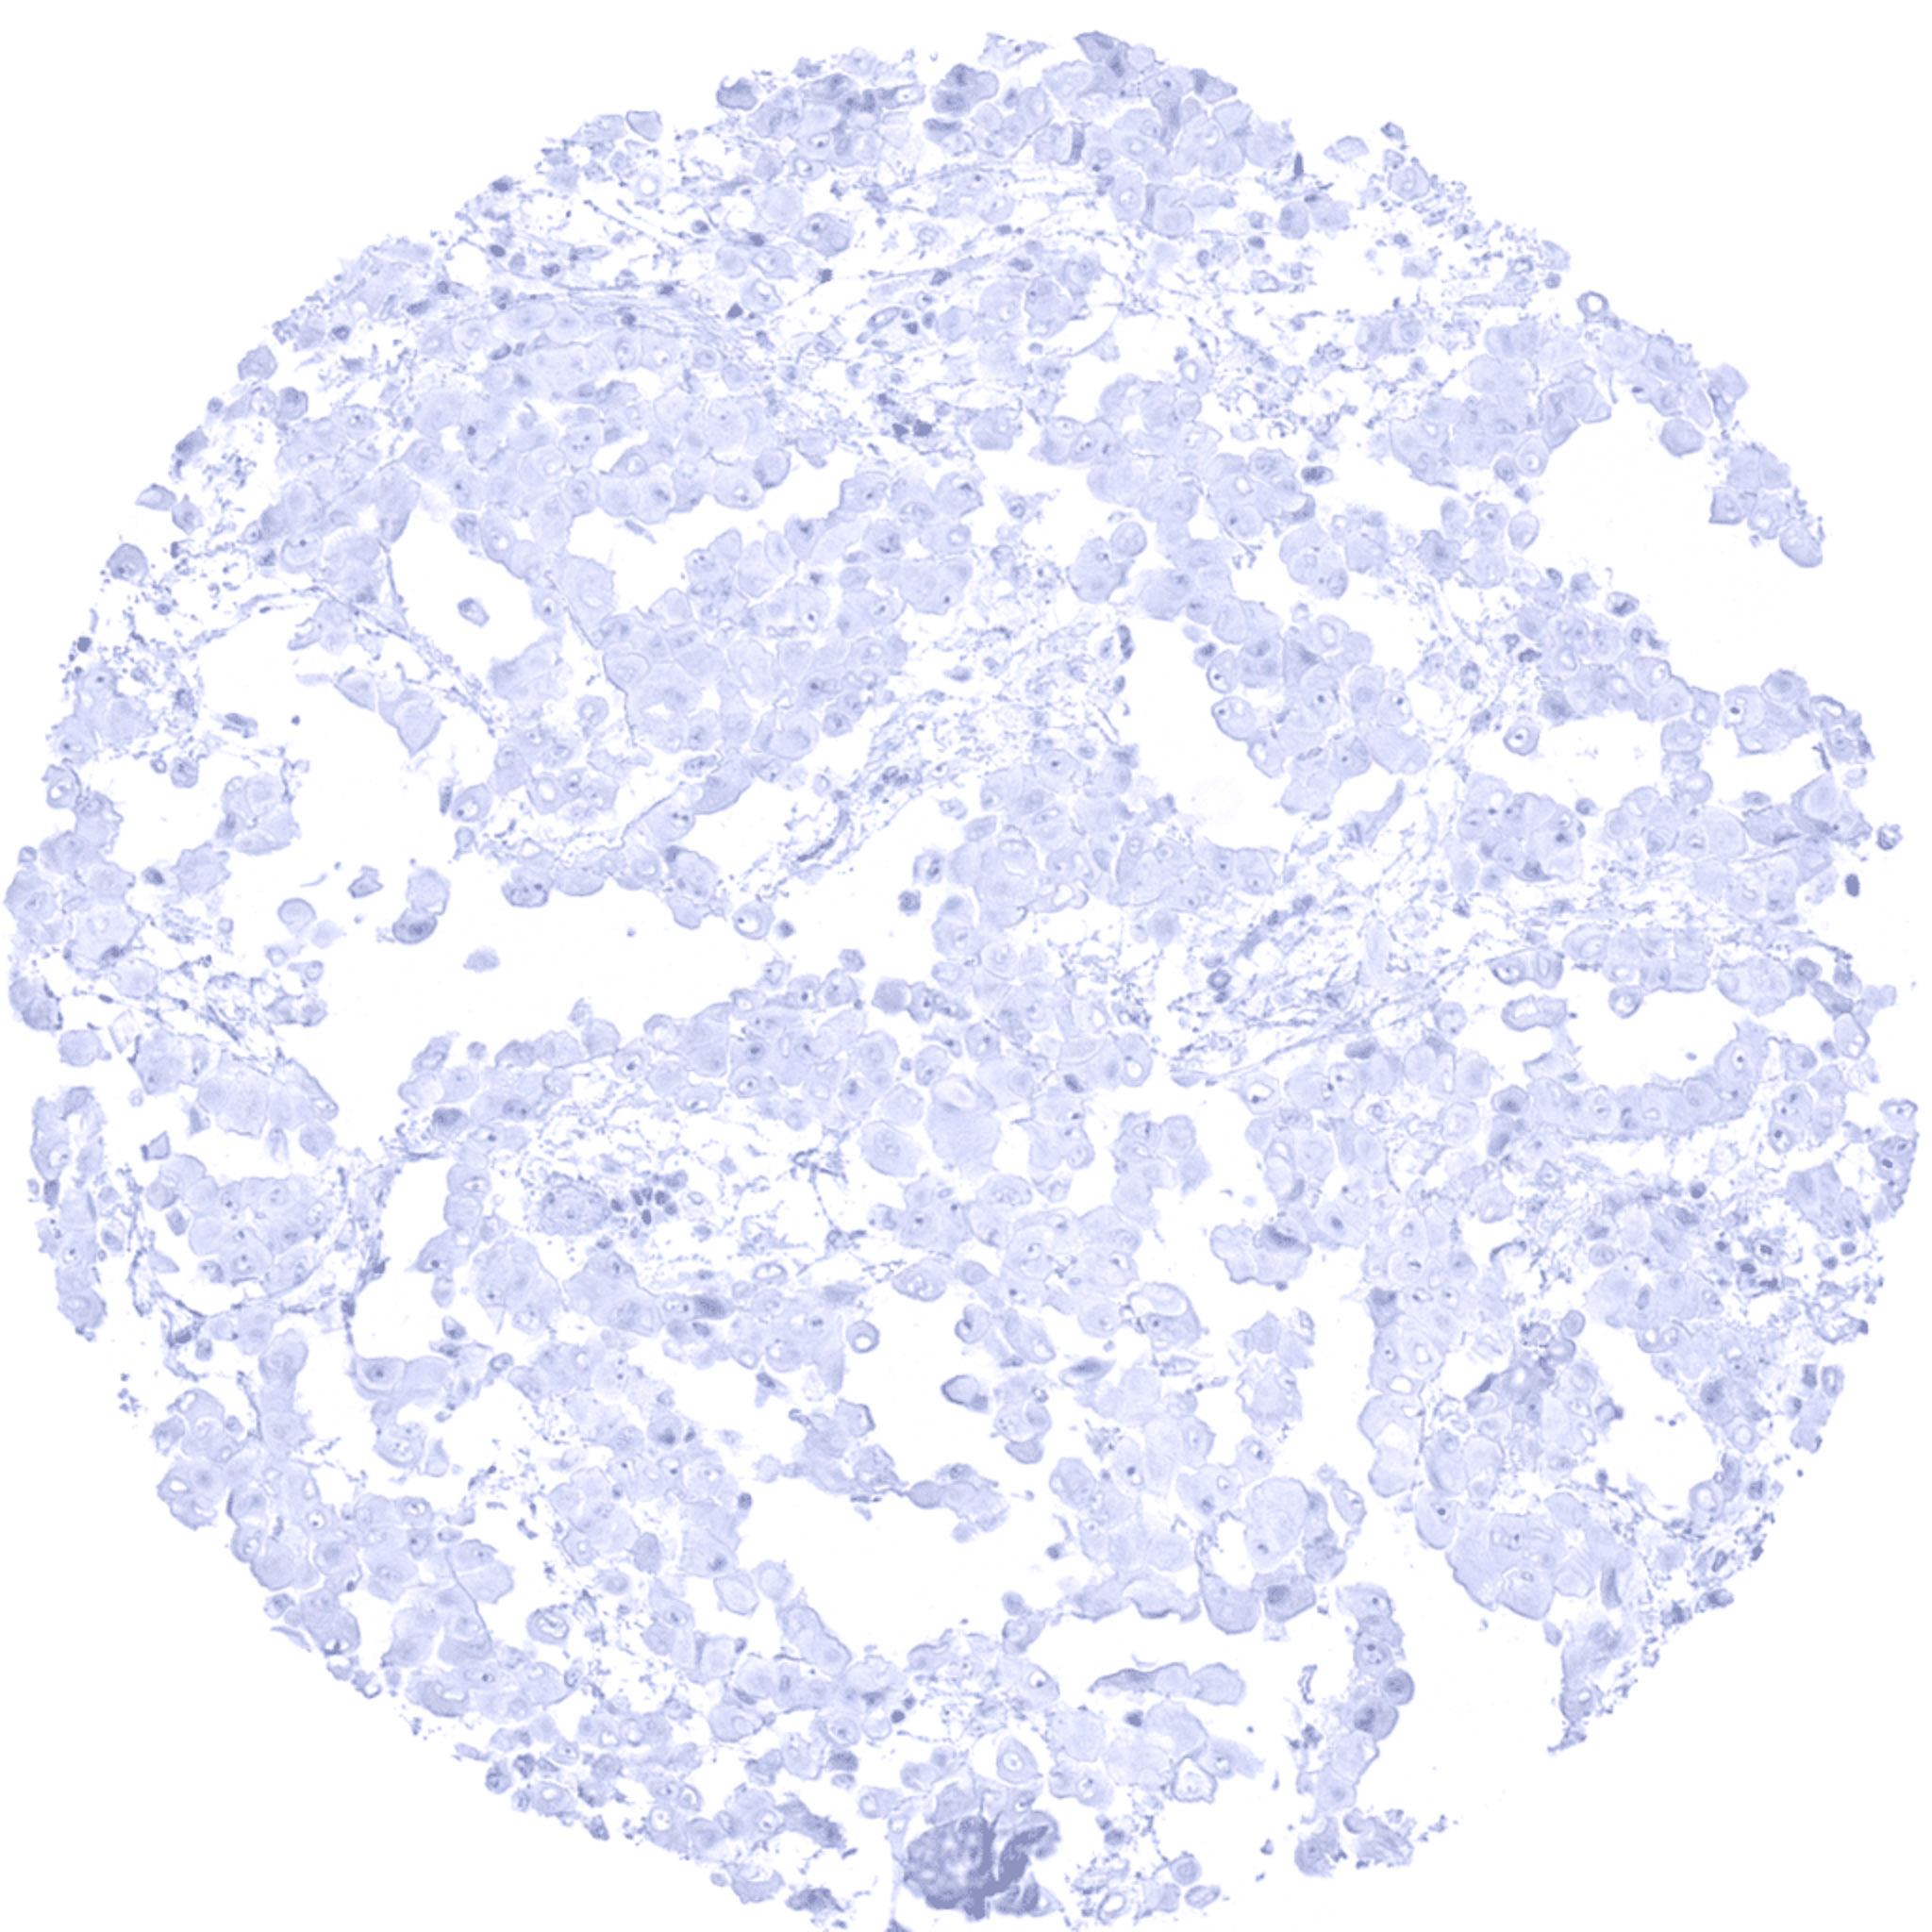

Stomach- Gastric adenocarcinoma (diffuse type) with strong S100P immunostaining of tumor cells.